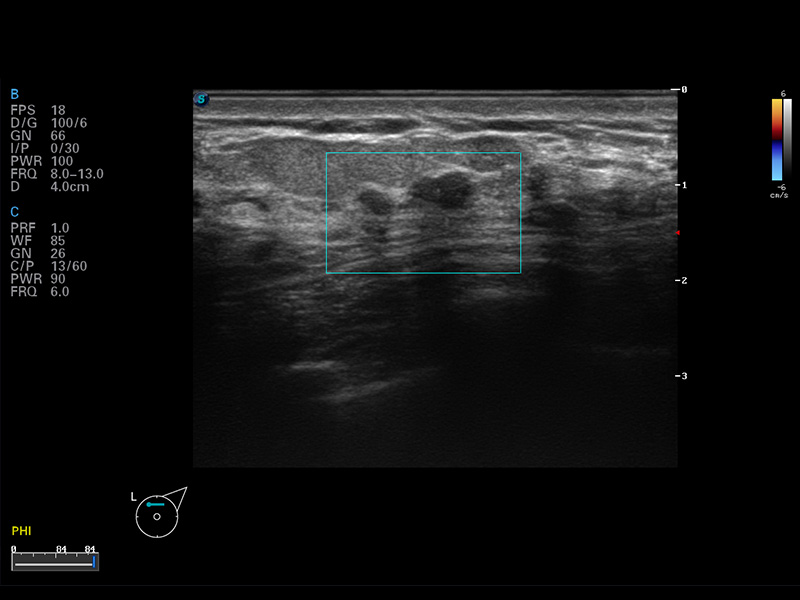

S8 EXP便攜式彩色多普勒超聲診斷儀是開立醫(yī)療研發(fā)的高端全身應(yīng)用型便攜彩超。高通道的VIS平臺(tái)融合可視化(Visual)、智能化(Intelligent)和人性化(Smart)的特點(diǎn),配以開立醫(yī)療自主研發(fā)生產(chǎn)的探頭大家族,使您能夠快速、準(zhǔn)確的獲得病人信息,提高工作效率的同時(shí)減輕疲勞。

μ-Scan微米成像